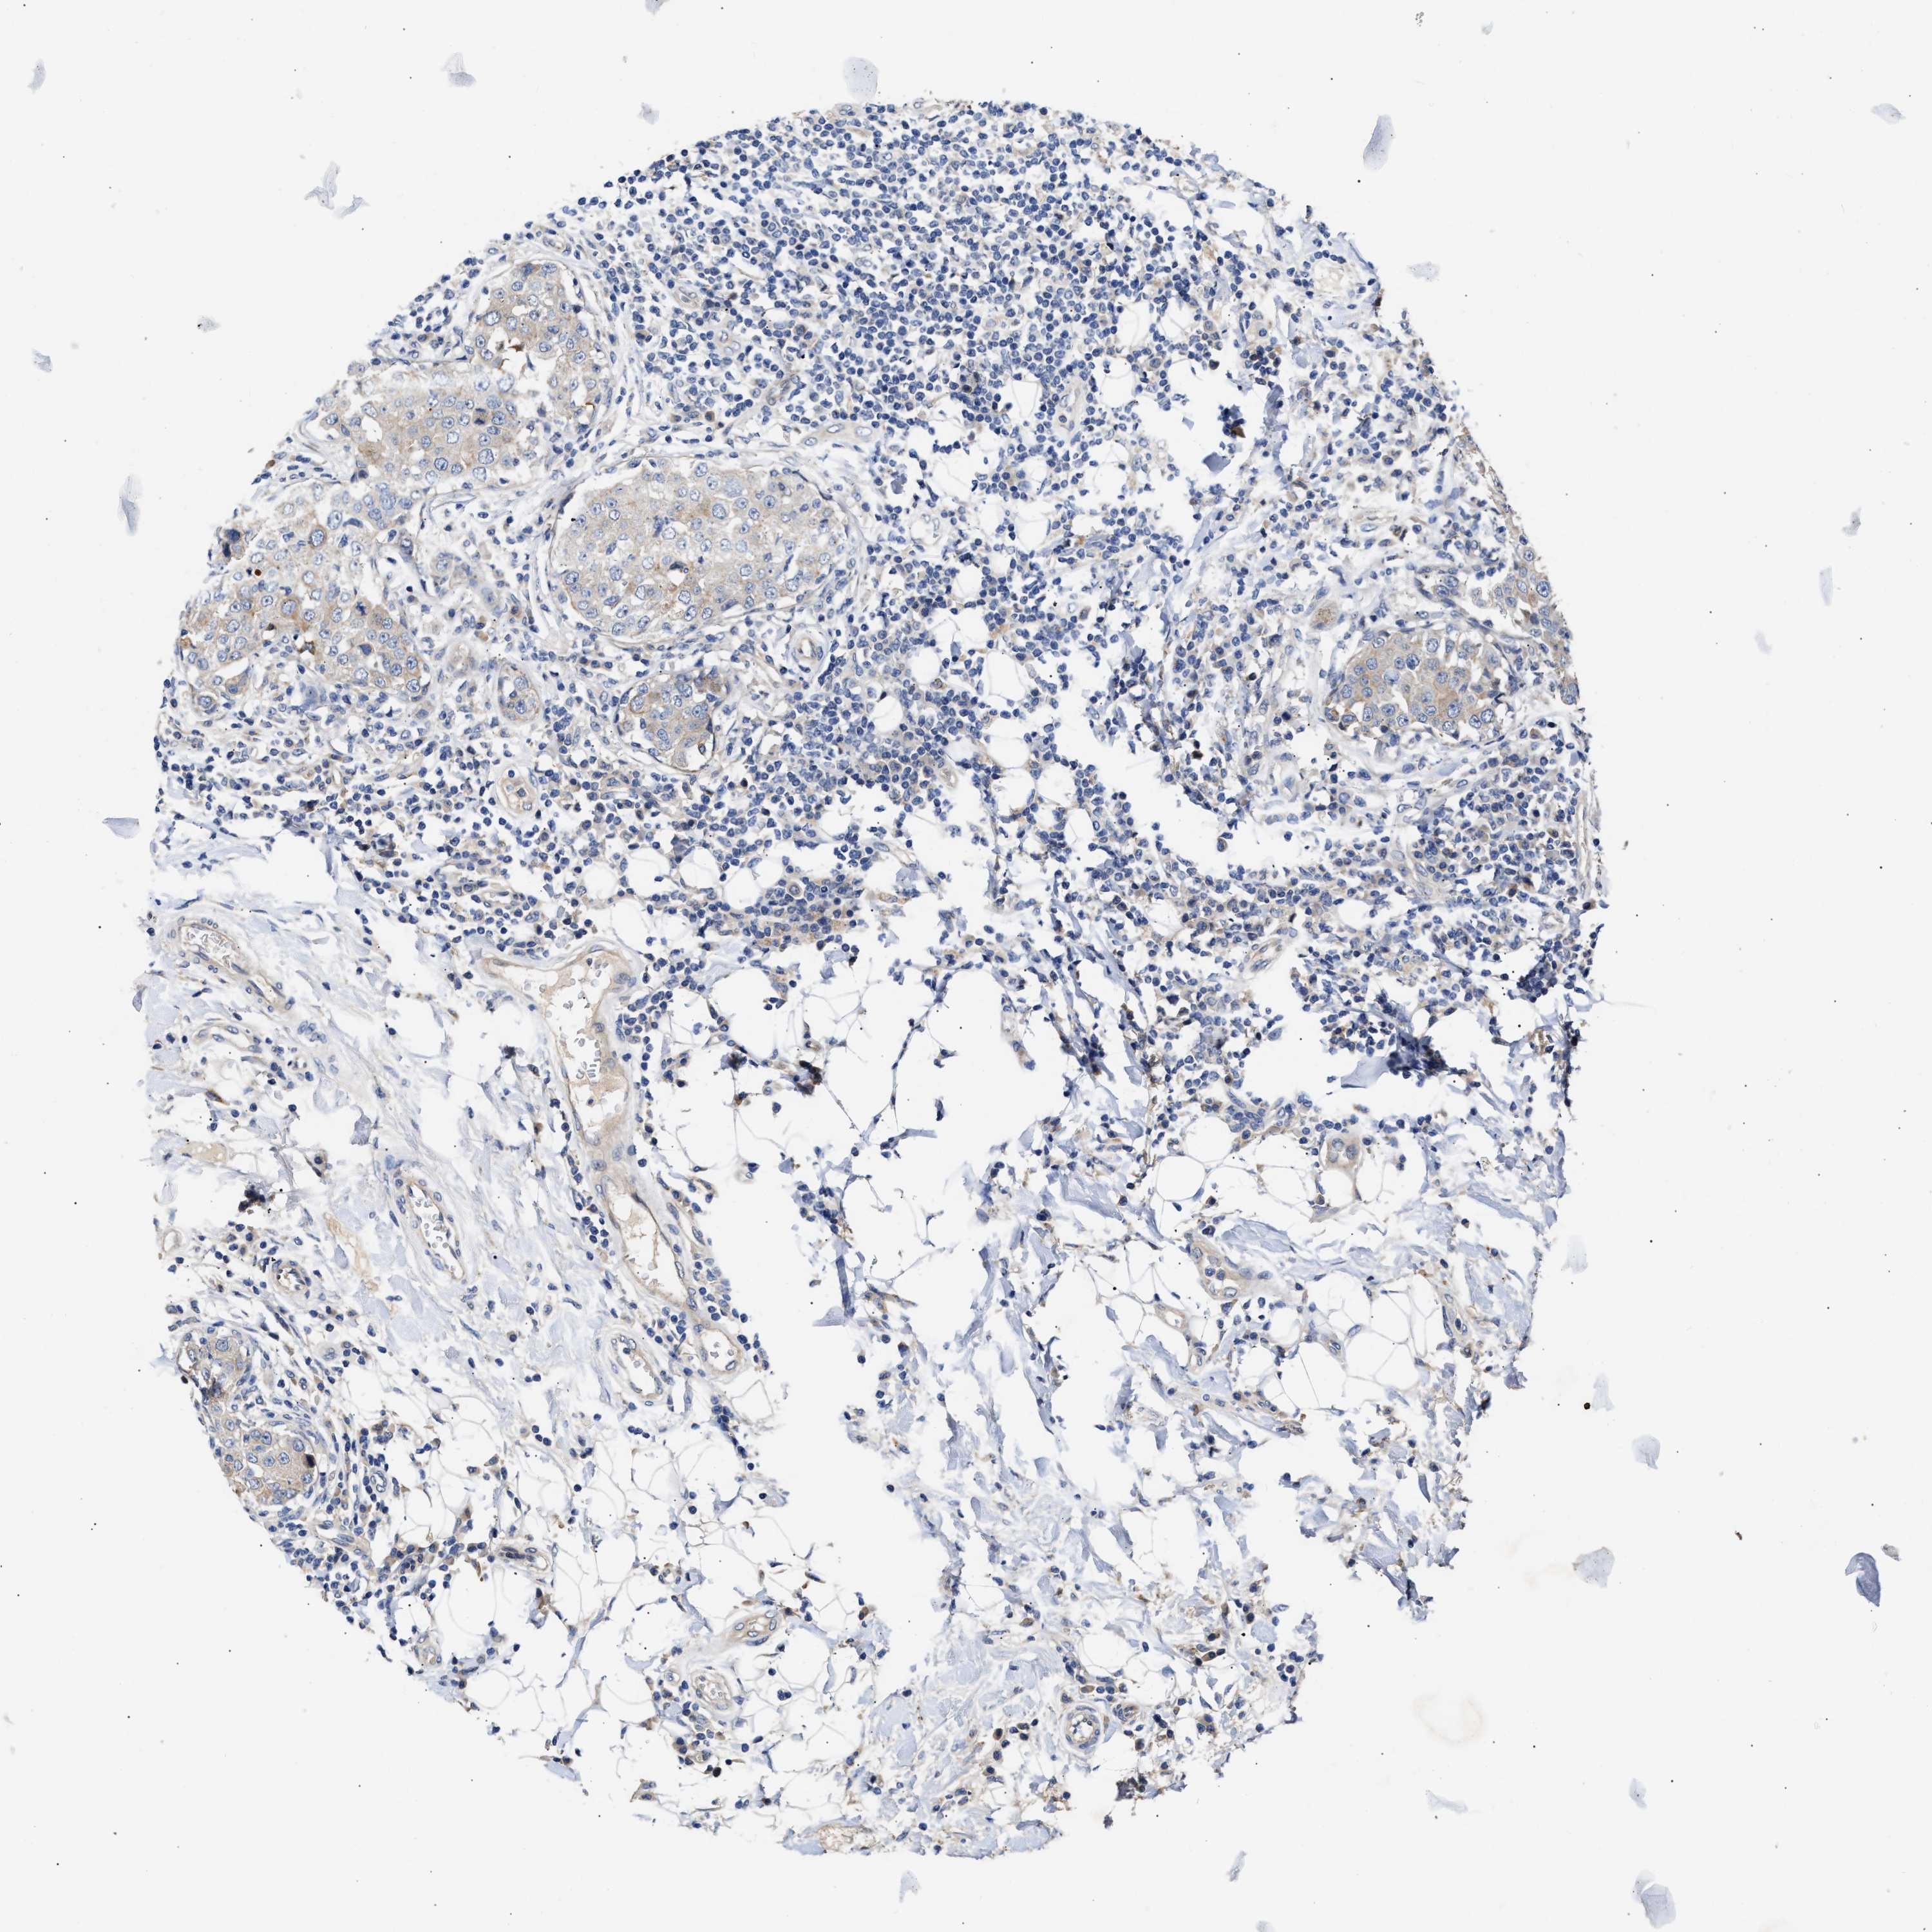

CANCER BREAST CANCER Show tissue menu

BRCA TCGA BRCA VALIDATION PROTEIN EXPRESSION

ANTIBODIES

AND

VALIDATION